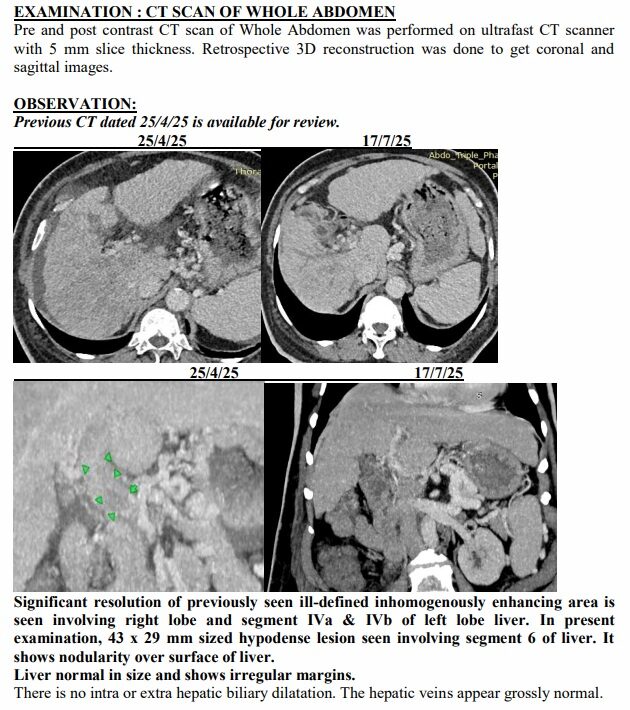

Yet just three months later, on another afternoon in July, the same family stared at a different scan. The tumours had shrunk to one patch. Blood was flowing again. The swelling was gone. Even the alarming tumour marker that had shot up to 1,000 ng/mL had fallen to 10, back in the safe zone. For a man who had been fading fast, it was a turnaround no one in the room dared to predict.

The July scan sealed what they were already feeling at home. The many shadows in his liver had shrunk into one. His abdomen, once swollen with fluid, was flat again. His numbers, which had scared even seasoned oncologists, were suddenly within range.

A senior radiologist who reviewed both reports told this correspondent, “Such a reversal in advanced liver cancer is extremely rare. Clinically, it borders on the unbelievable.”